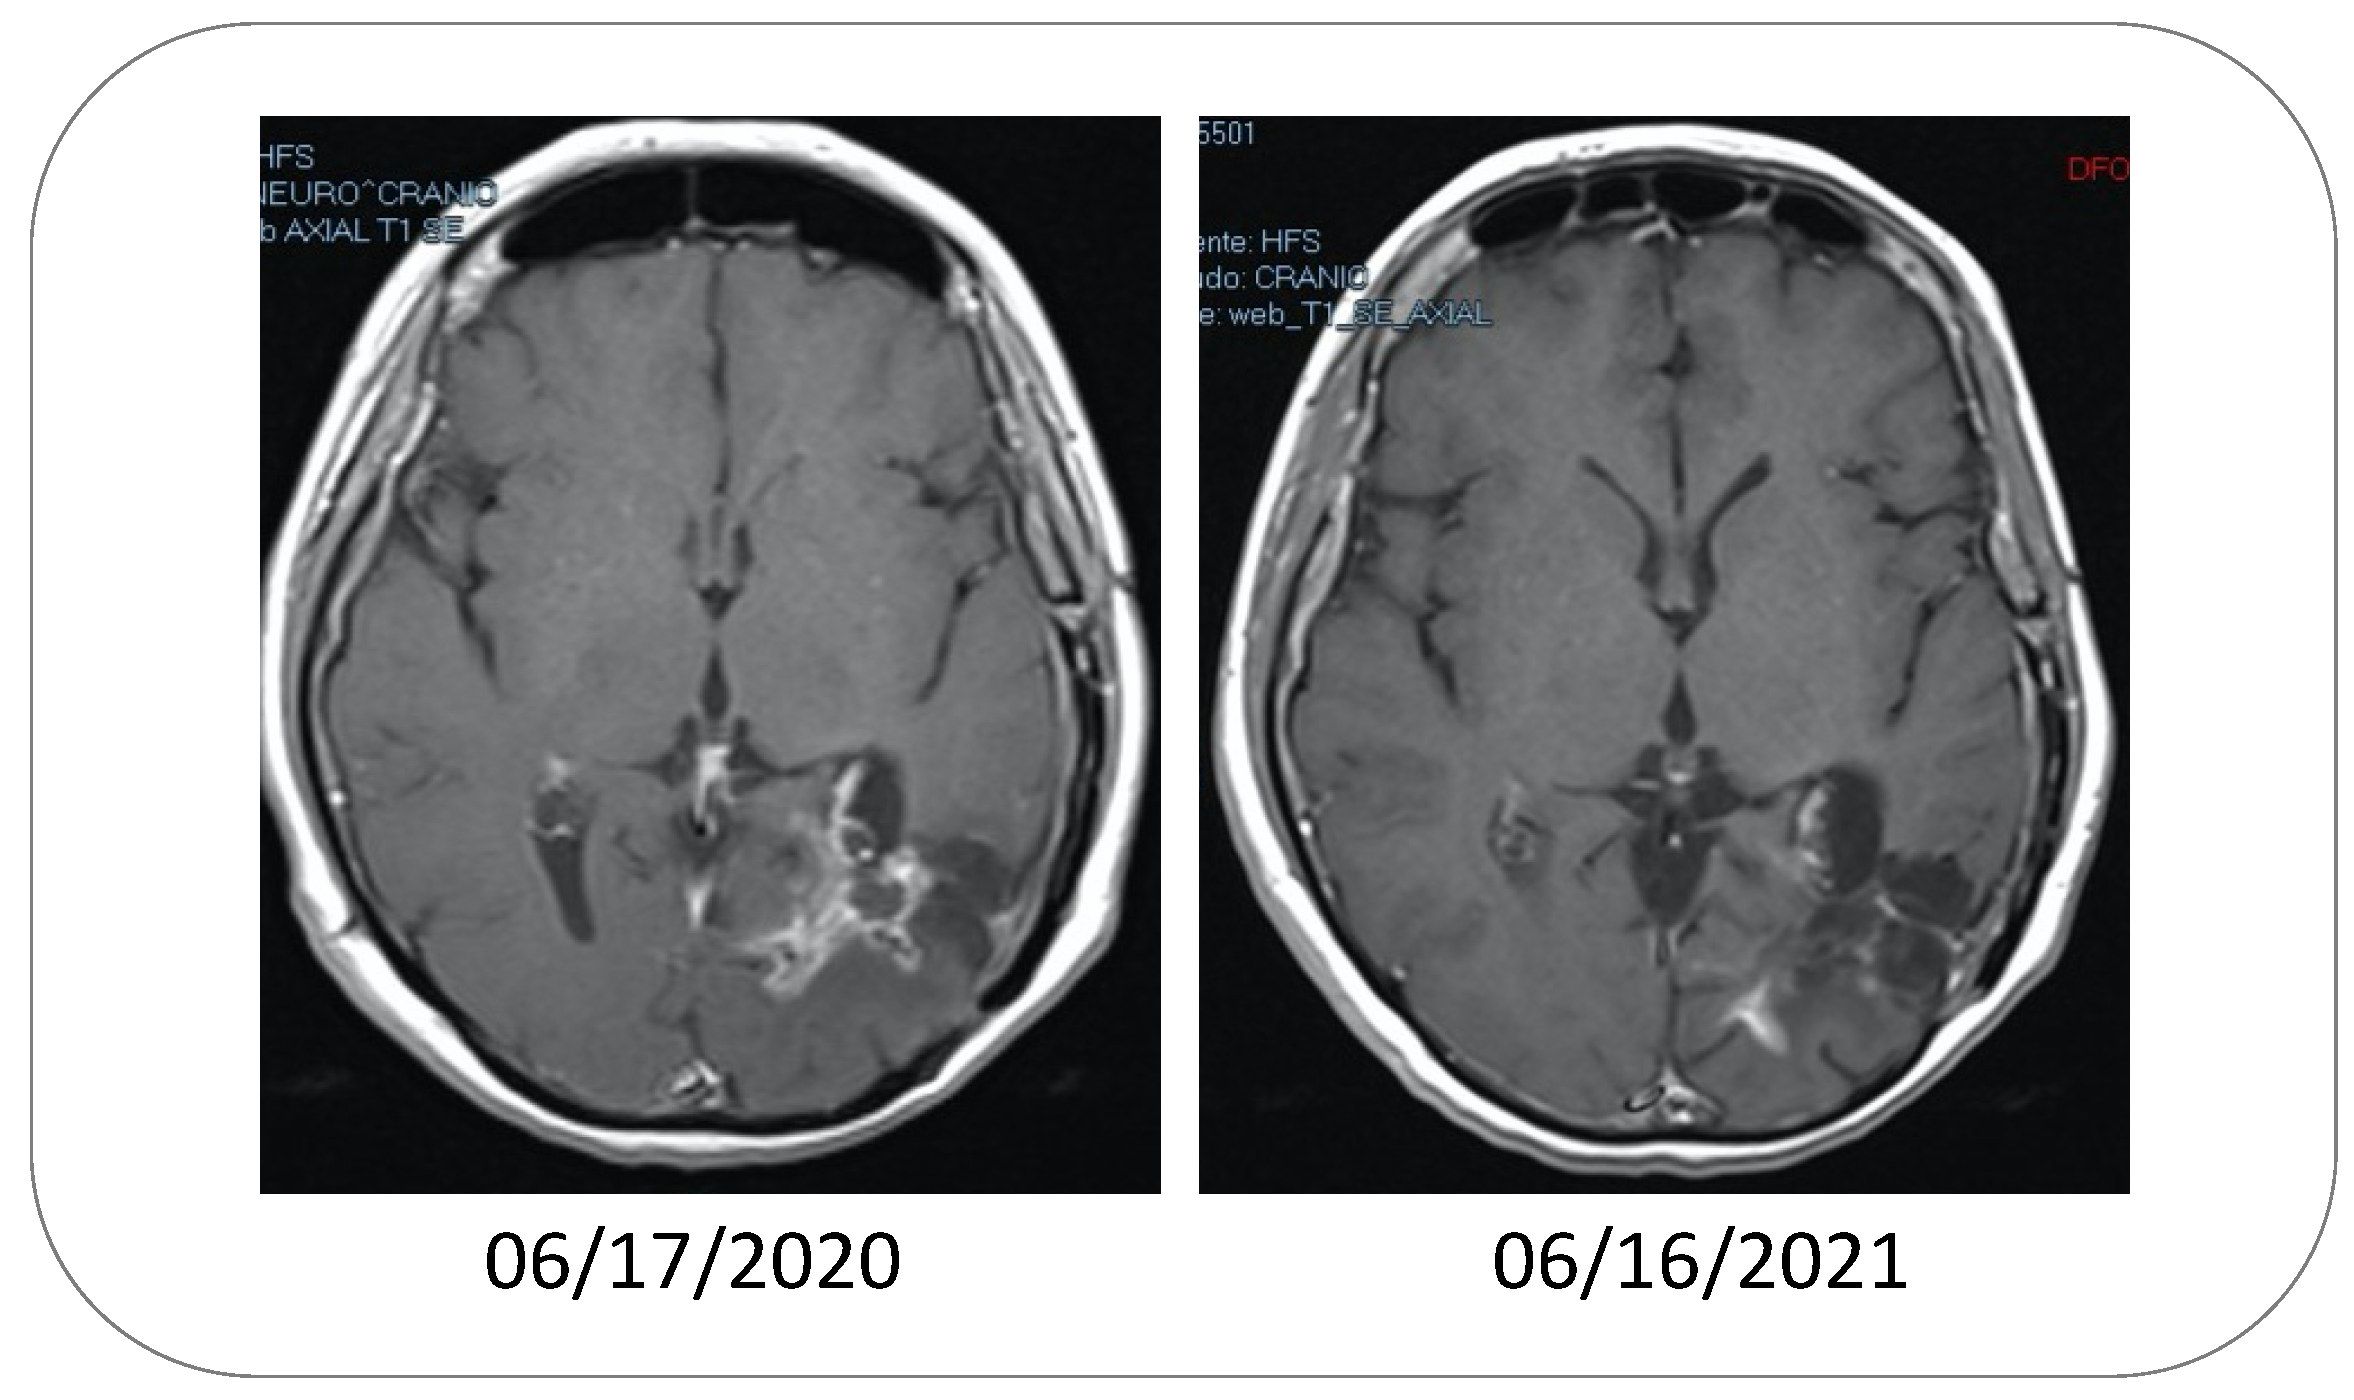

4.1. Intranasal POH as Monotherapy

- Da Fonseca, C.O.; Simão, M.; Lins, I.R.; Caetano, R.O.; Futuro, D.; Quirico-Santos, T. Efficacy of monoterpene perillyl alcohol upon survival rate of patients with recurrent glioblastoma. J. Cancer Res. Clin. Oncol. 2010, 137, 287–293. [Google Scholar] [CrossRef] [PubMed]

- Da Fonseca, C.O.; Teixeira, R.M.; Silva, J.C.T.; Fischer, J.D.S.D.G.; Meirelles, O.C.; Landeiro, J.A.; Quirico-Santos, T. Long-term outcome in patients with recurrent malignant glioma treated with Perillyl alcohol inhalation. Anticancer Res. 2013, 33, 5625–5631. [Google Scholar]

- Da Fonseca, C.; Soares, I.P.; Clemençon, D.S.; Rochlin, S.; Cardeman, L.; Quirico-Santos, T. Perillyl alcohol inhalation concomitant with oral temozolomide halts progression of recurrent inoperable glioblastoma: A case report. J. Histol. Histopathol. 2015, 2, 12. [Google Scholar] [CrossRef]